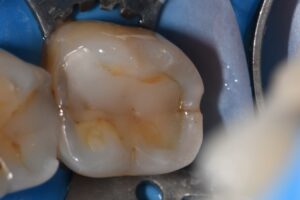

Complex reconstruction of tooth #18MODB featuring M and D marginal ridge vertical hairline fractures and secondary caries.

Matrix-in-Matrix system used for the efficient reconstruction of the D marginal ridge. The M ridge was restored using the Garrison Compositight 3D Fusion Green ring (wide prep) as the MB extension obviated the placement of a conventional blue ring. This still had great retention/staying power on the clamped tooth.

Single shade restoration courtesy of Kuraray Clearfil Majesty ES-2 Universal U with Voco Final Touch tint applied (brown only). Occlusion conformative.